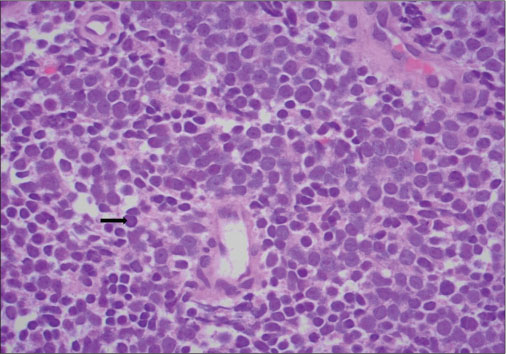

Prostatic biopsy was suggestive of small cell carcinoma [Figure 6].

| Figure.6:(H and E, ×400) showing multiple small round neoplastic cells (black arrow) with high nuclear to cytoplasmic ratio and scanty cytoplasm with hyperchromatic nuclei suggestive of small cell carcinoma